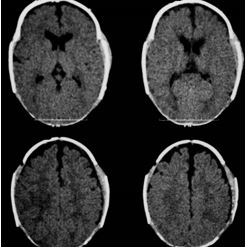

Mas doutor, quando é preciso de tomografia do crânio? Quase nunca, é solicitado quando existe alguma dúvida e mais ainda nas craniossinostoses sindrômicas.

> Escafocefalia, é a sinostoses mais comum, vista mais no sexo masculino,o que acontece é o fechamento da sutura sagital levando o crânio ao formato de barco. A cirurgia é indicada de preferencia antes do sexto mês de vida, mas se a criança tiver mais idade, não impede de ser operado.

> Trigonocefalia, é o fechamento precoce da sutura metópica, o formato do crânio é em forma de pera o qual realiza compressão do lobo frontal que pode levar aumento da pressão intracraniana em até 20% dos casos. Crianças com mais de 5 anos que não foram operados, tem literatura que fala em dificuldade do aprendizado.

> Plagiocefalia, é o fechamento precoce da sutura coronal unilateral (plagiocefalia anterior) ou da sutura lambdoide (plagiocefalia posterior), afeta mais o sexo feminino e o lado direito é mais afetado. A criança tem um rostro em “arlequim” já que uma das órbitas esta retraída para cima e para tras.

> Braquicefalia, é o fechamento prematura de ambas suturas coronais ou lambdoides.